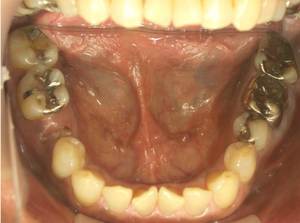

インプラントの症例 2.インプラントと矯正治療を行った例

治療前

治療後